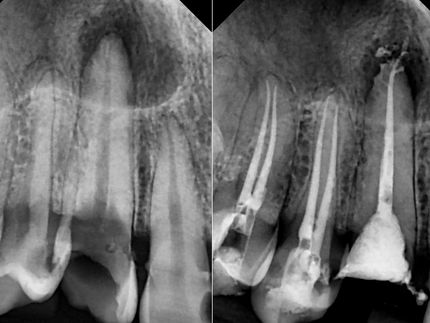

Endodontic treatment aims to repair and save a badly damaged infected tooth. the procedure involves removing the damaged pulp or nerve, cleaning disinfecting it, and then filling and sealing it.

The following cases were done using MTWO rotary endodontic instruments by VDW for fast and safe root canal preparation.